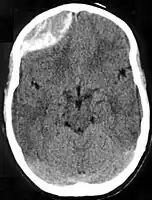

| Epidural hematoma as seen on a CT scan with overlying skull fracture. Note the biconvex shaped collection of blood. There is also bruising with bleeding on the opposite side of the brain. | |

Epidural hematomas usually appear convex in shape because their expansion stops at the skull's sutures, where the dura mater is tightly attached to the skull. Thus, they expand inward toward the brain rather than along the inside of the skull, as occurs in subdural hematomas. Most people also have a skull fracture.[3]